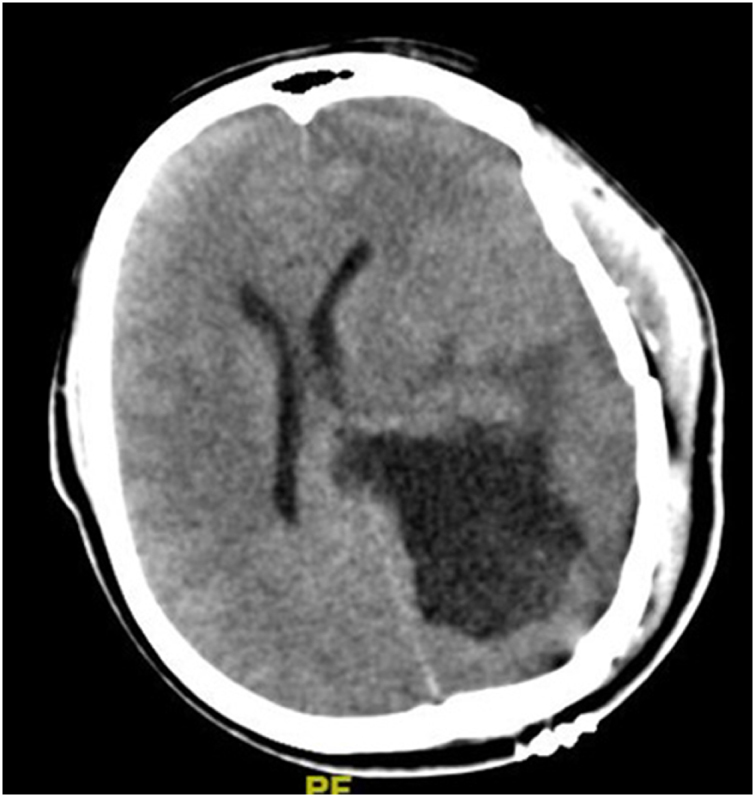

Introduction and importance: Postoperative cyst formation is a rare but significant complication following central nervous system (CNS) tumor resection. This case report describes a 14-year-old girl who developed a postoperative cyst after glioma excision, successfully managed through a minimally invasive approach.

Case presentation: A 14-year-old female presented with headache and seizures. Magnetic Resonance Imaging (MRI) revealed a mass in the trigonal region. She underwent surgical resection of the tumor. On postoperative day 7, she developed a symptomatic cyst at the tumor bed. The cyst was drained, resulting in symptomatic improvement. Follow-up assessments confirmed her clinical recovery.